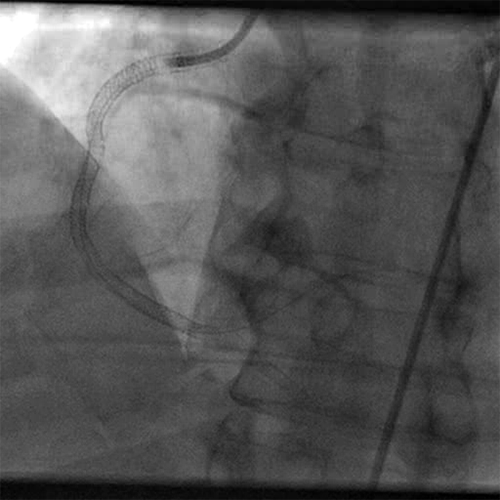

• Significant angiographic improvement was observed post mechanical thrombectomy

• Post ANGIOJET thrombus grade was 3 (Cine 3: Post AngioJet)